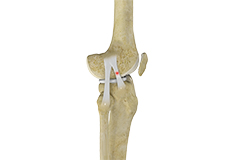

Bones of the Knee

The knee is a hinge joint made up of two bones, the thighbone (femur) and shinbone (tibia). There are two round knobs at the end of the femur called femoral condyles that articulate with the flat surface of the tibia called the tibial plateau. The tibial plateau on the inside of the leg is called the medial tibial plateau and on the outside of the leg, the lateral tibial plateau.

The two femoral condyles form a groove on the front (anterior) side of the knee called the patellofemoral groove. A small bone called the patella sits in this groove and forms the kneecap. It acts as a shield and protects the knee joint from direct trauma.

A fourth bone called the fibula is the other bone of the lower leg. This forms a small joint with the tibia. This joint has very little movement and is not considered a part of the main joint of the knee.